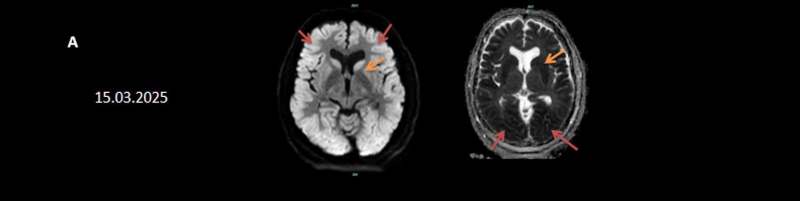

- A) Bilateral serebral kortekste (oklar) ve bazal ganglionlarda (oklar) yaygın DAG hiperintens, ADC hipointens difüzyon kısıtlamaları görülüyor.

15.03.2025